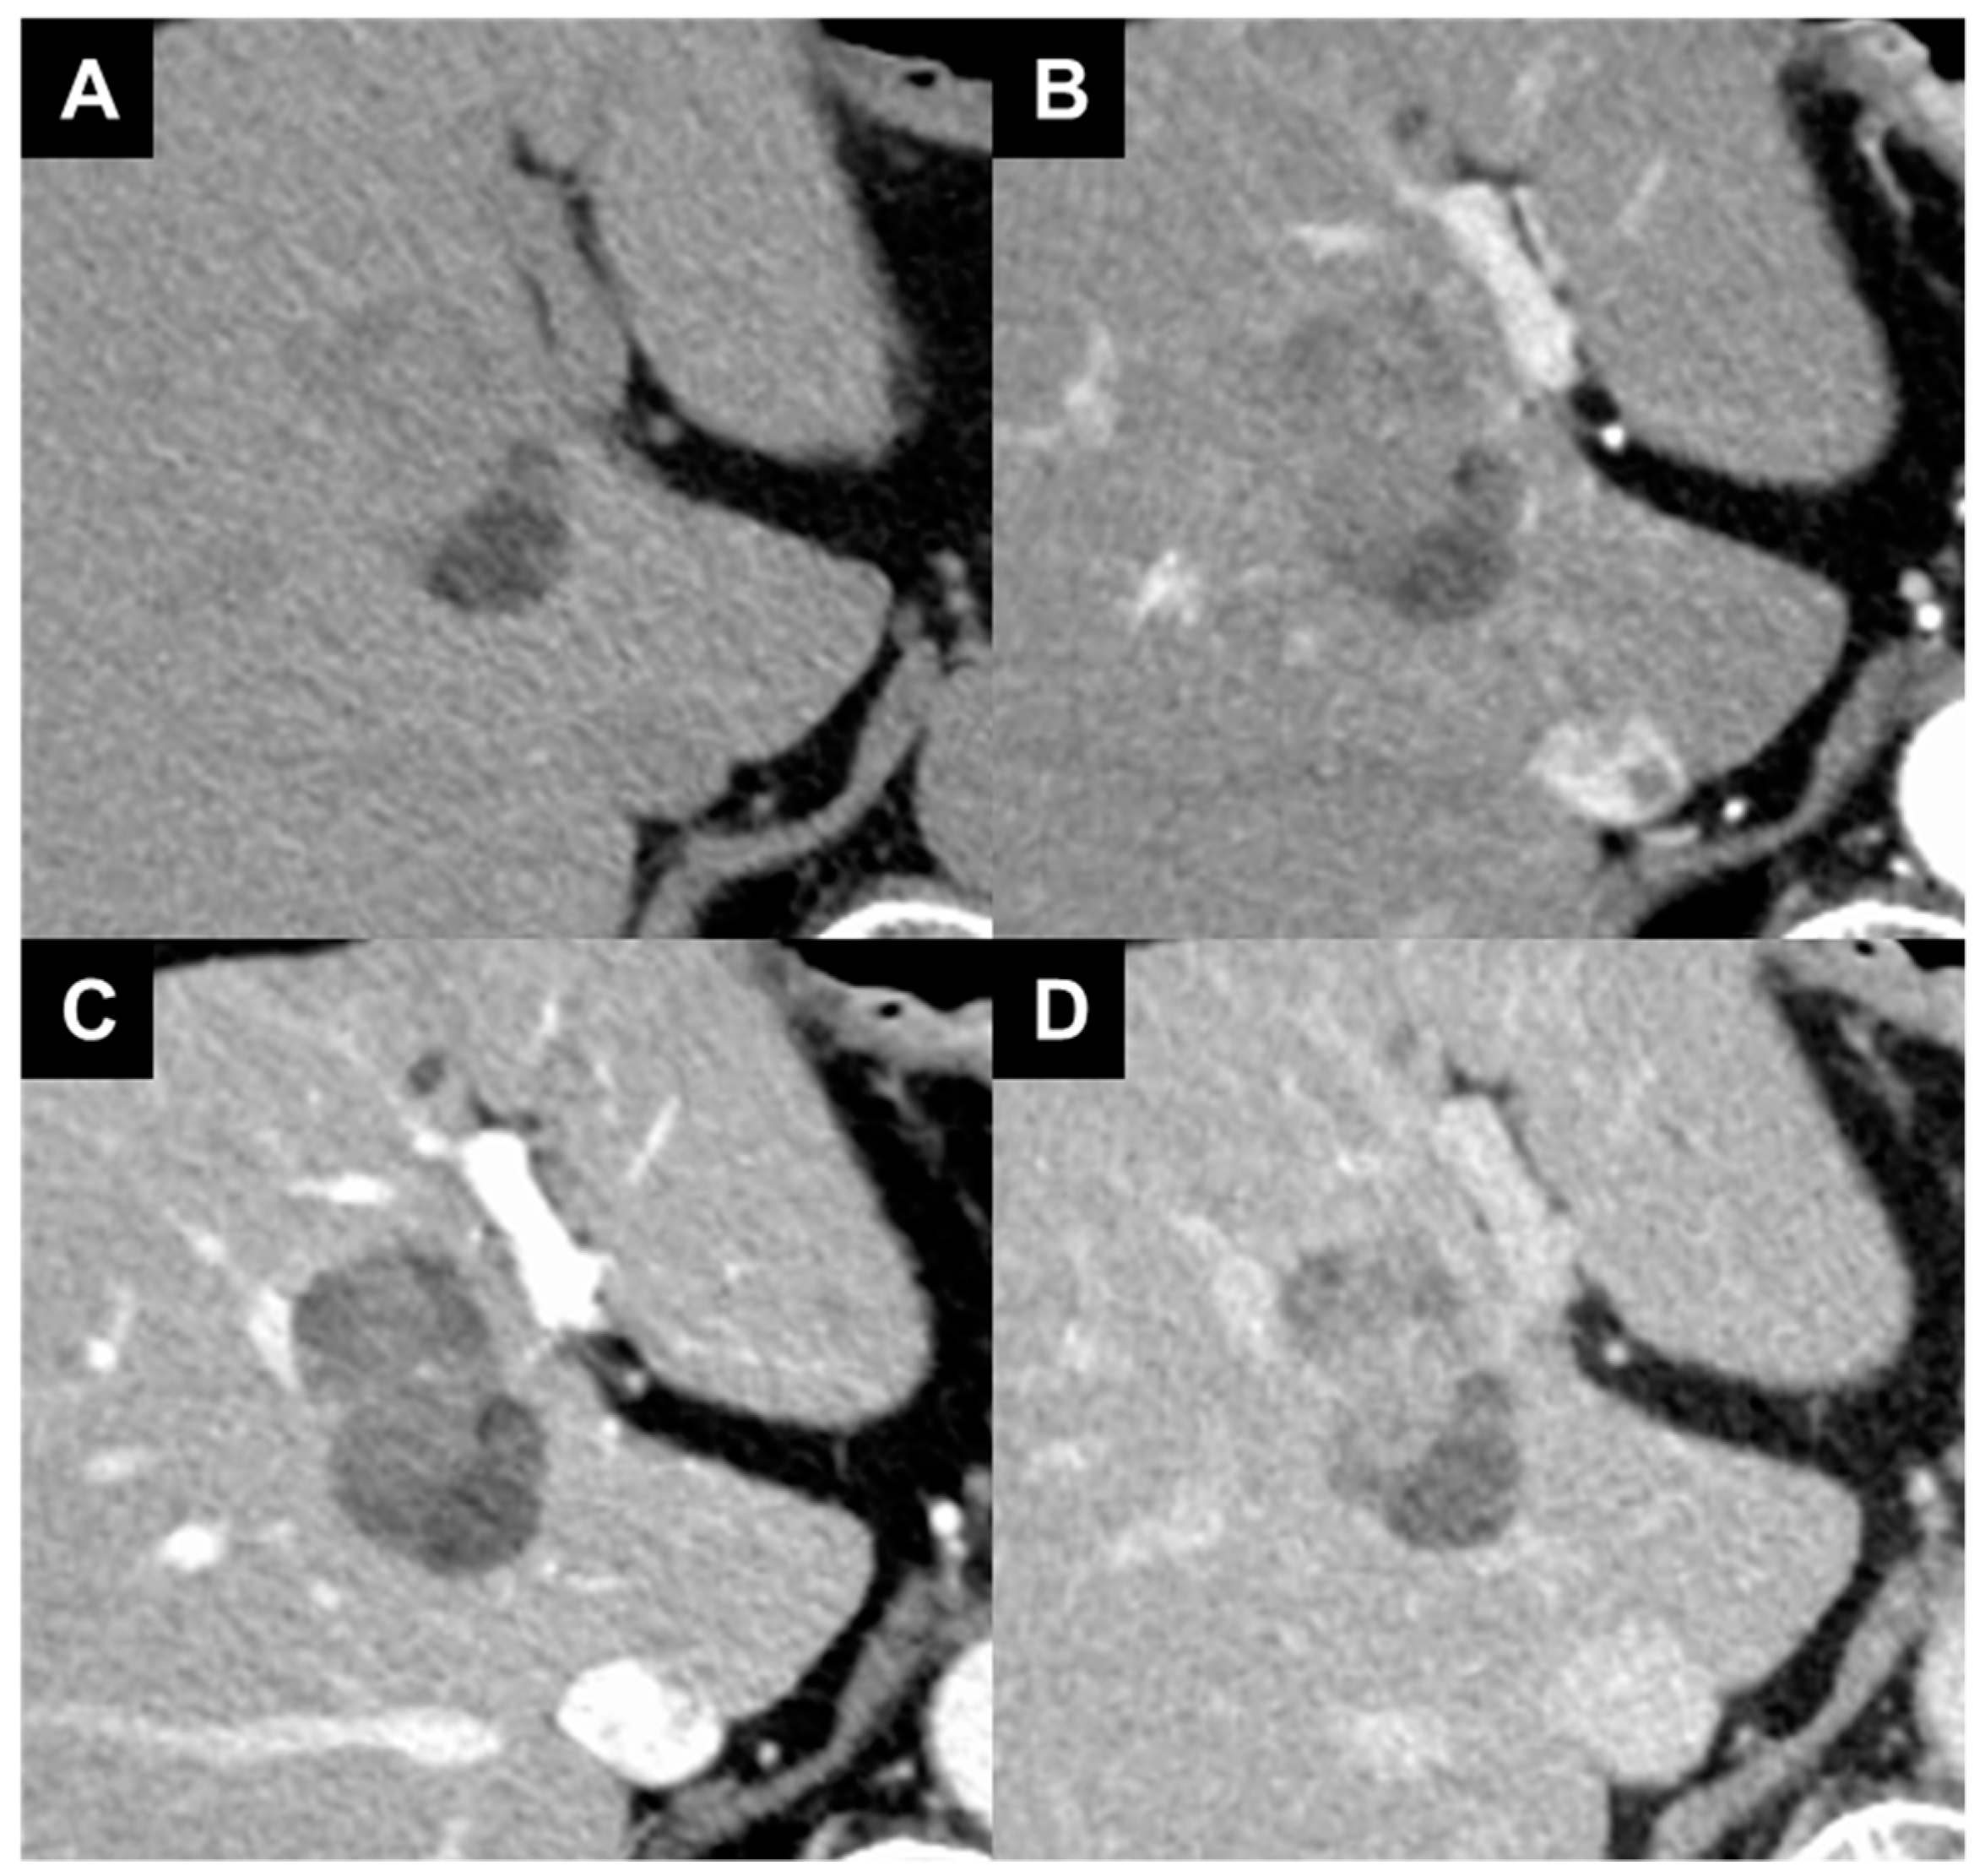

- Muraishi, N.; Kawamura, Y.; Akuta, N.; Shindoh, J.; Matsumura, M.; Okubo, S.; Fujiyama, S.; Hosaka, T.; Saitoh, S.; Sezaki, H.; et al. The Impact of Lenvatinib on Tumor Blood Vessel Shrinkage of Hepatocellular Carcinoma during Treatment: An Imaging-Based Analysis. Oncology 2023, 101, 134–144. [Google Scholar] [CrossRef]